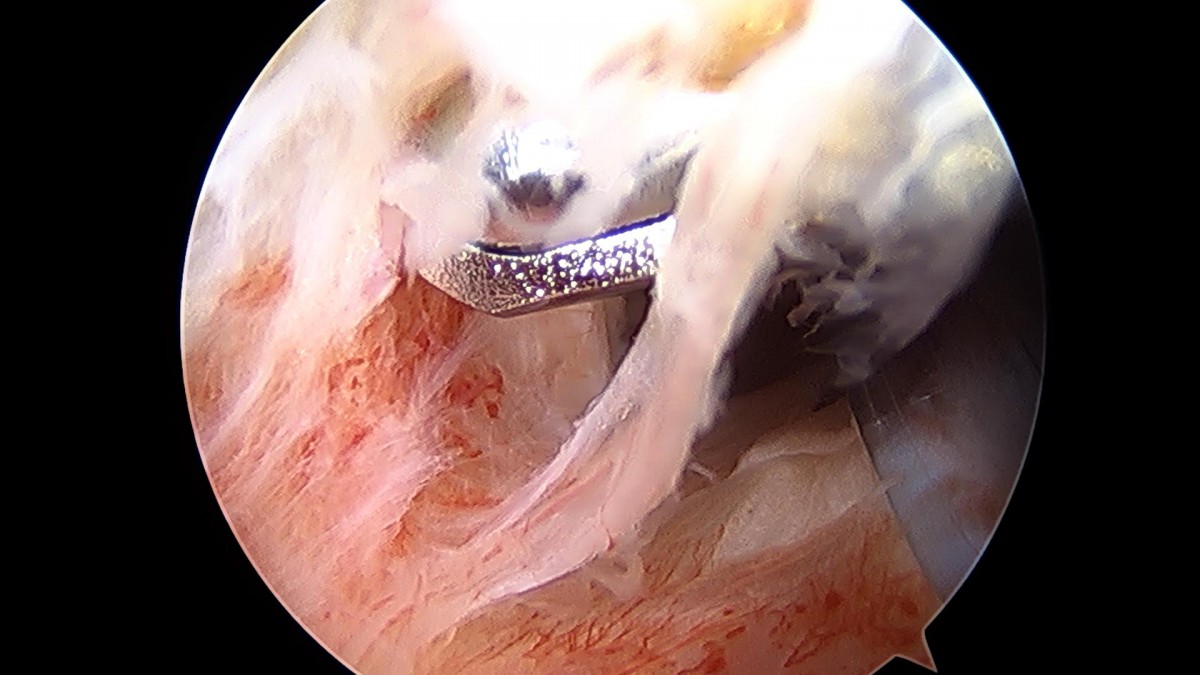

이재상원장님 어깨 회전근개 봉합술 (1094)이현O 환자

작성자 최고관리자 댓글 0건 조회 1,224회 작성일 22-02-23 14:11